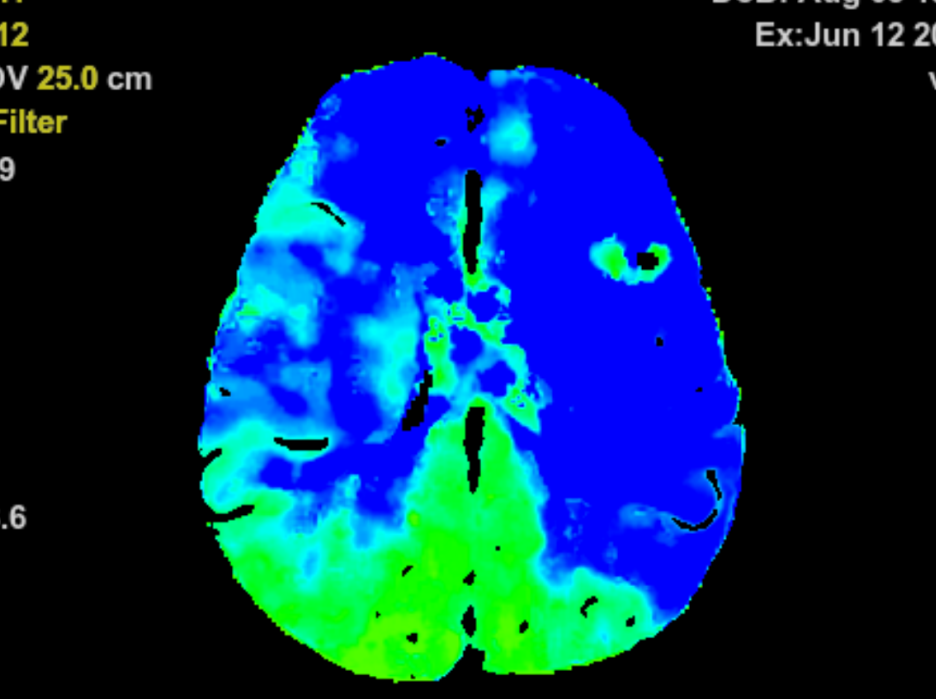

术后脑血流灌注成像图显示,黄色和红色区域基本消失,大脑供血恢复明显

2小时后,新的供血通路成功建立。术后脑血流灌注成像图显示,此前的缺血区域供血基本恢复了正常。患者也表示,眼睛看东西清晰了很多,表明手术疗效初步显现。